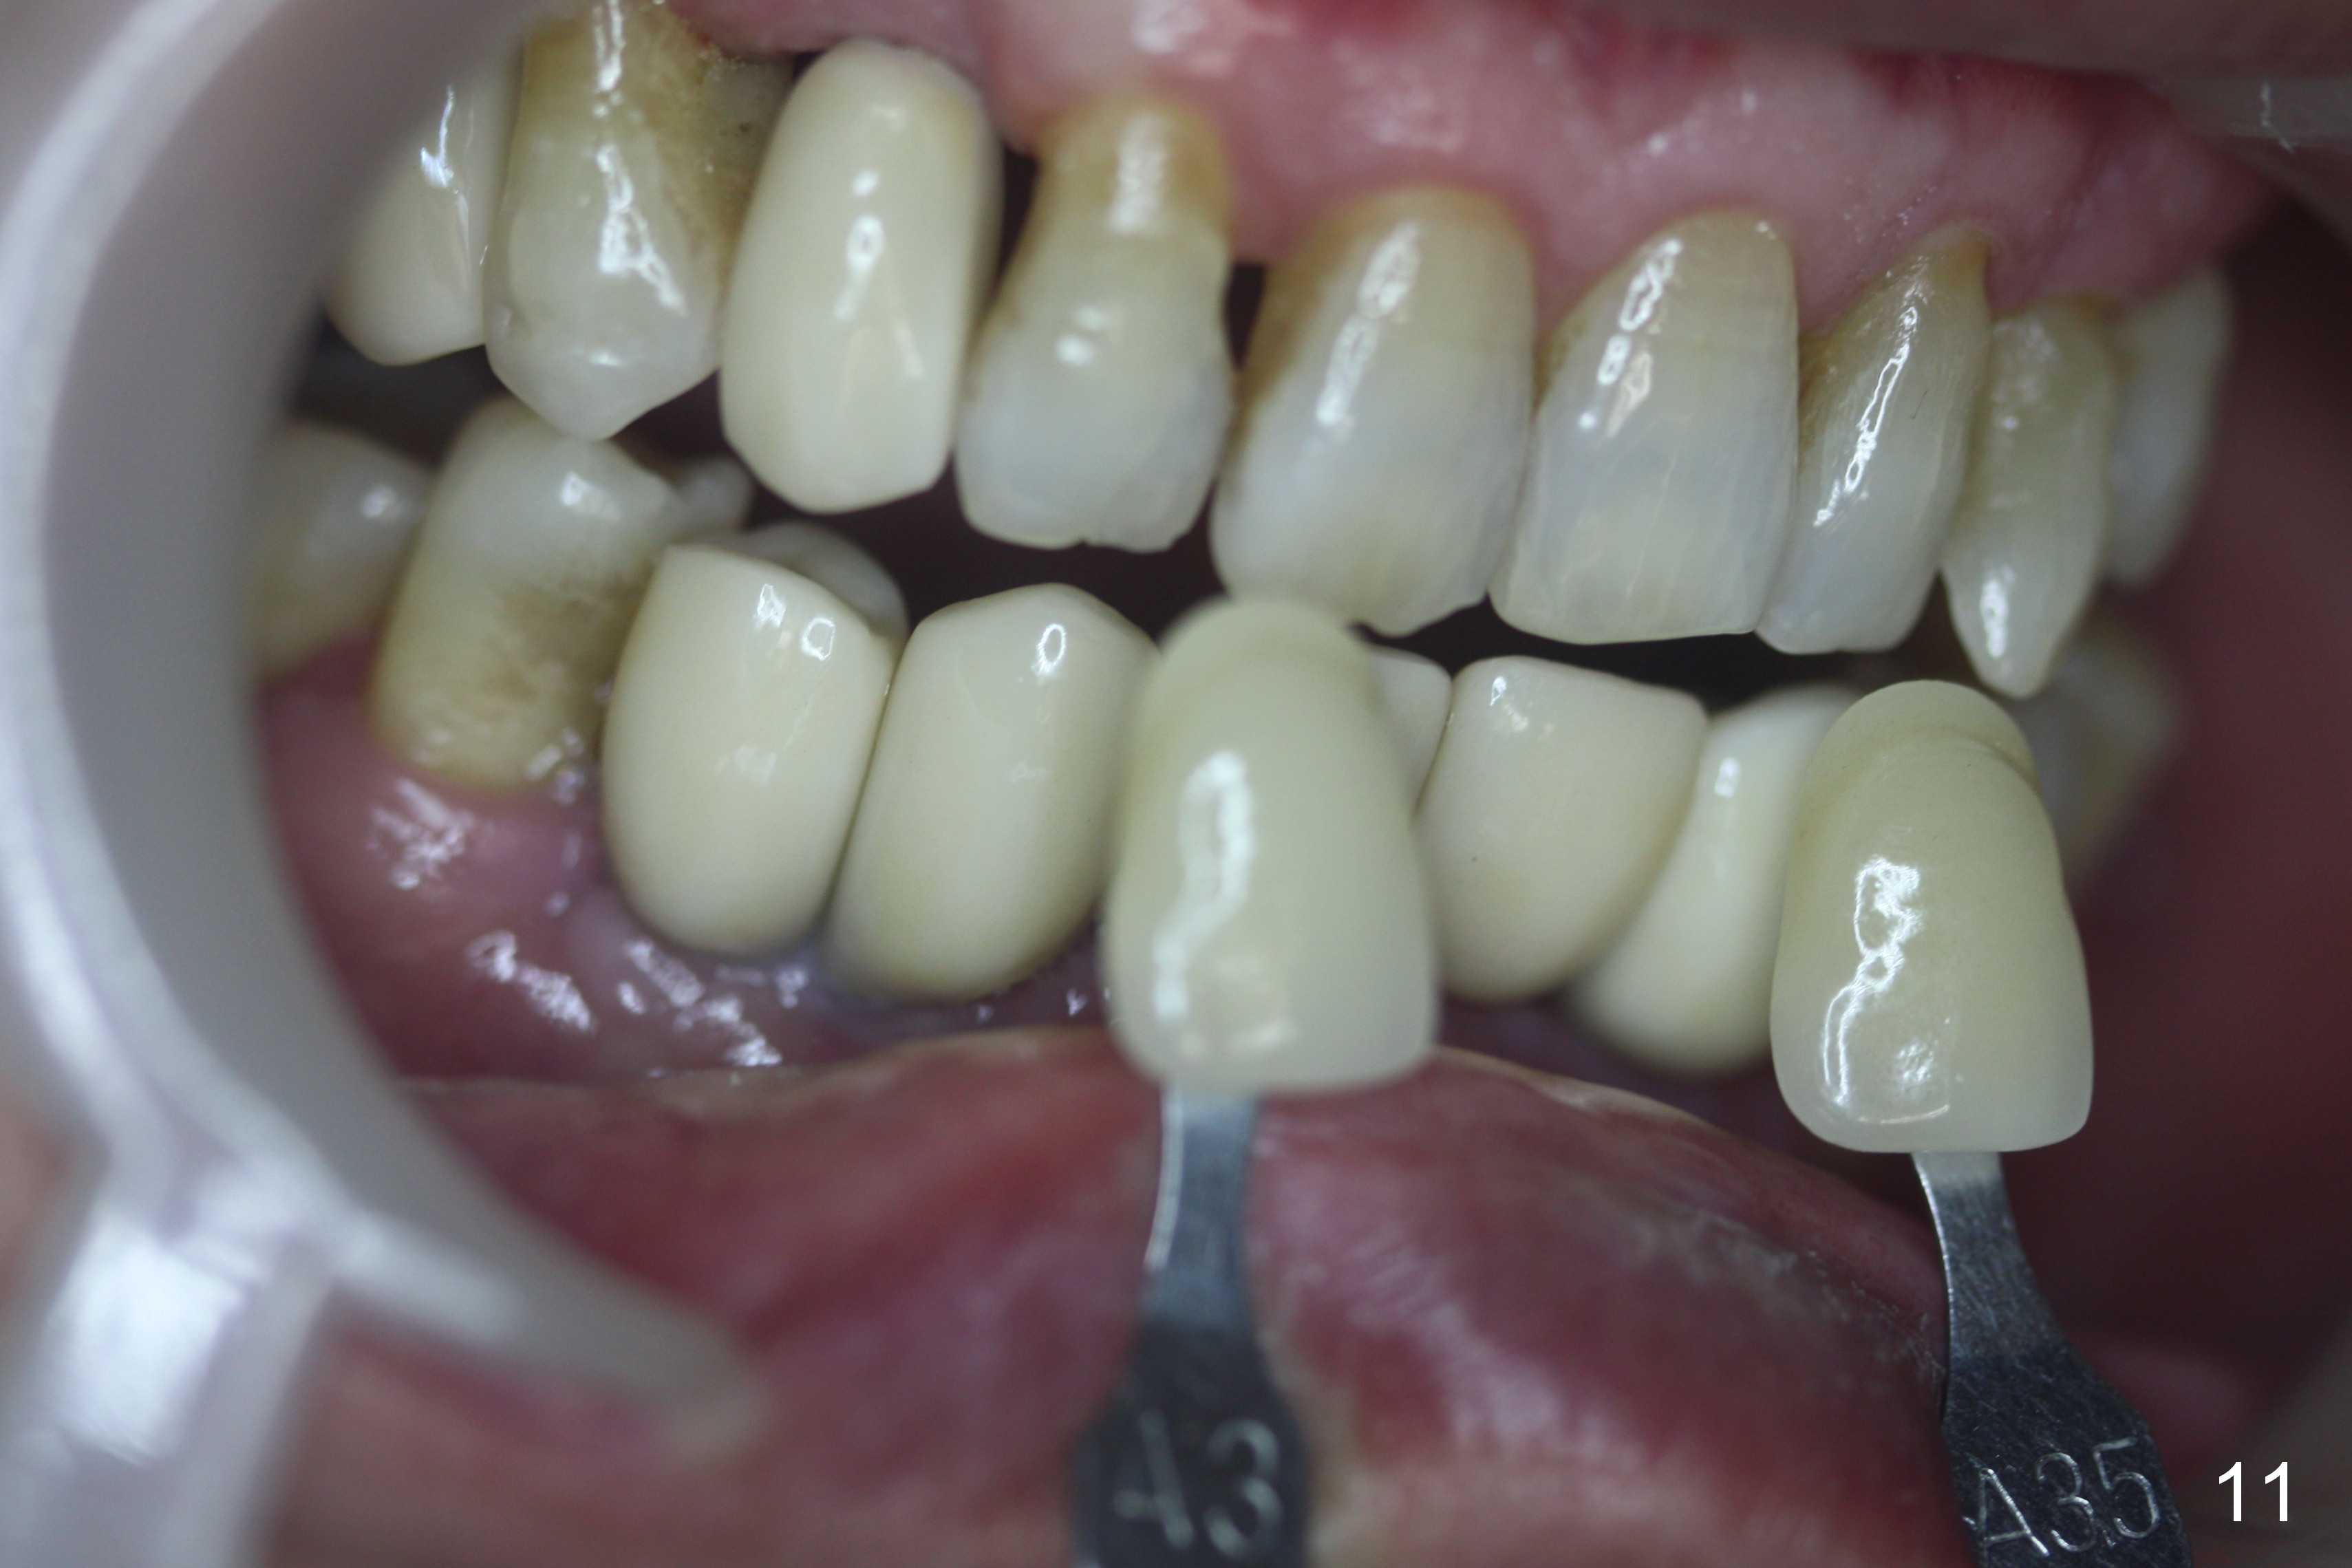

When the final crowns are seated, the shade is off.  It appears that C3 is appropriate (Fig.10,11).  Please make the crowns more transparent.